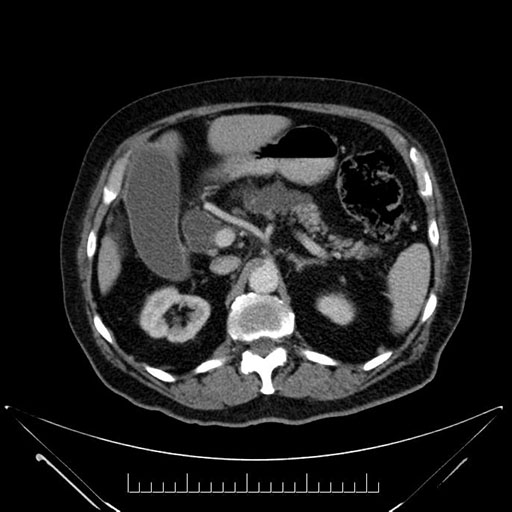

Imaging Analysis

Look through the patient's CT scan to identify any areas of concern for the necessary procedure.

Based on your CT findings, which issue(s) would give reason for "planned slowing down moment(s)" in this case?